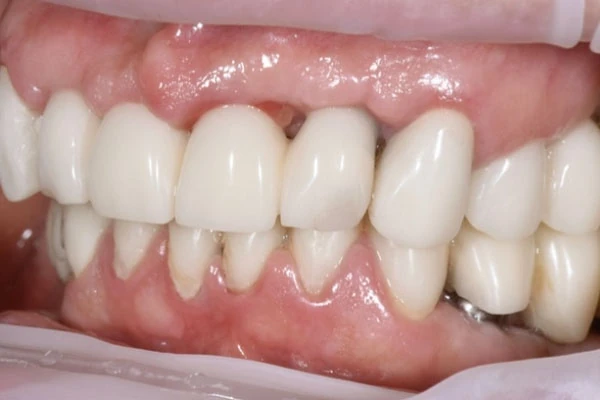

Пластика десен (гингивопластика) - хирургическая коррекция дефектов десен, восстановление и изменение десневого контура. Вмешательство проводится под местной анестезией и позволяет решить как медицинские вопросы, так и вопросы эстетики.

- рецессии (оголение корня зуба)